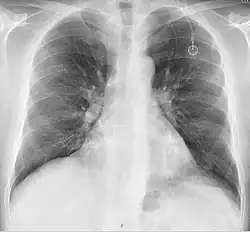

The port is usually inserted in the upper chest (known as a "chest port"), just below the clavicle or collar bone, with the catheter inserted into the jugular vein.

A port consists of a reservoir compartment (the portal) that has a silicone bubble for needle insertion (the septum), with an attached plastic tube (the catheter). The device is surgically inserted under the skin in the upper chest or in the arm and appears as a bump under the skin. It requires no special maintenance other than occasional flushing to keep clear. It is completely internal so swimming and bathing are not a problem. The catheter runs from the portal and is surgically inserted into a vein (usually the jugular vein or less optimally the subclavian vein). Ideally, the catheter terminates in the superior vena cava or the right atrium. This position allows infused agents to be spread throughout the body quickly and efficiently.

Ports can be put in the upper chest or arm. The exact positioning itself is variable as it can be inserted to avoid visibility when wearing low cut shirts, and to avoid excess contact due to a backpack or bra strap. The most common placement is on the upper right portion of the chest, with the catheter itself looping through the right jugular vein, and down towards the patient's heart.